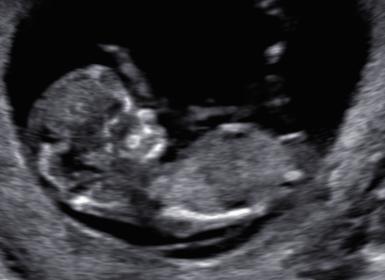

Just finished with NT scan and by lmp im 11w6d (although clinic said 12 weeks) and baby measures ahead at 12w5d. Any more thoughts with these? I have a video too but cant figure out how to blank out my name in it lol.

Attachment 27789Attachment 27790Attachment 27791Attachment 27792Attachment 27793Attachment 27794Attachment 27795

Wanted to update that i got my Mat21 results back and we are having a girl :)

THat is great news! Sorry I missed your recent pics, they were super girly too!!! :)